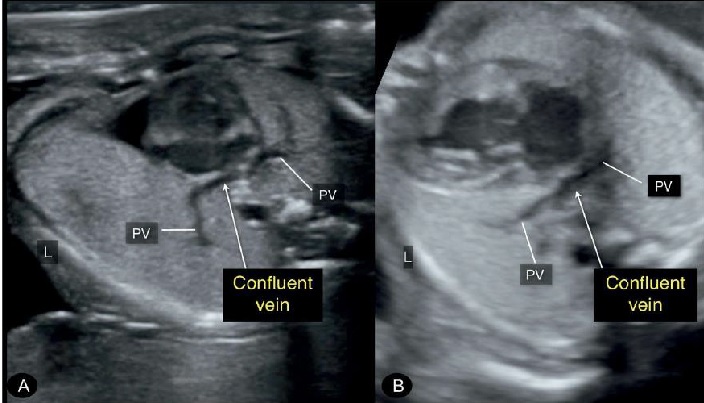

Hình 3: Mặt cắt ngang ngực 4 buồng tim. Hình ảnh bất thường hồi lưu tĩnh mạch phổi hoàn toàn (TAPVR). Chú ý, tĩnh mạch thu thập (confluent vein) phía sau tâm nhĩ trái (LA) nơi mà cả 4 tĩnh mạch phổi đổ gộp vào. Tĩnh mạch thu thập cùng với các tĩnh mạch phổi cho ra “dấu hiệu nhánh con” (“twig sign”). Hình ảnh 4 buồng tim trong hình vẽ là bình thường, nhưng trong nhiều trường hợp của TAPVR sẽ có hình ảnh tâm nhĩ trái hẹp và tâm thất trái hẹp hơn so tâm nhĩ phải và tâm thất phải.

Hình 4: Mặt cắt ngang ngực 4 buồng tim. Thai nhi (A) và thai nhi (B) đều có bất thường hồi lưu tĩnh mạch phổi toàn phần (TAPVR). Lưu ý hình ảnh tĩnh mạch thu thập (confluent vein) ở phía sau tim nơi các tĩnh mạch phổi (PV) đổ vào, thay vì đổ vào tâm nhĩ trái. Ngoài TAPVR ở thai (A) còn có mỏm tim bên phải (dextrocardia) và kiểu hình bên phải (right isomerism), ở thai (B) còn có thiểu sản sản tim trái (hypoplastic left heart syndrome).